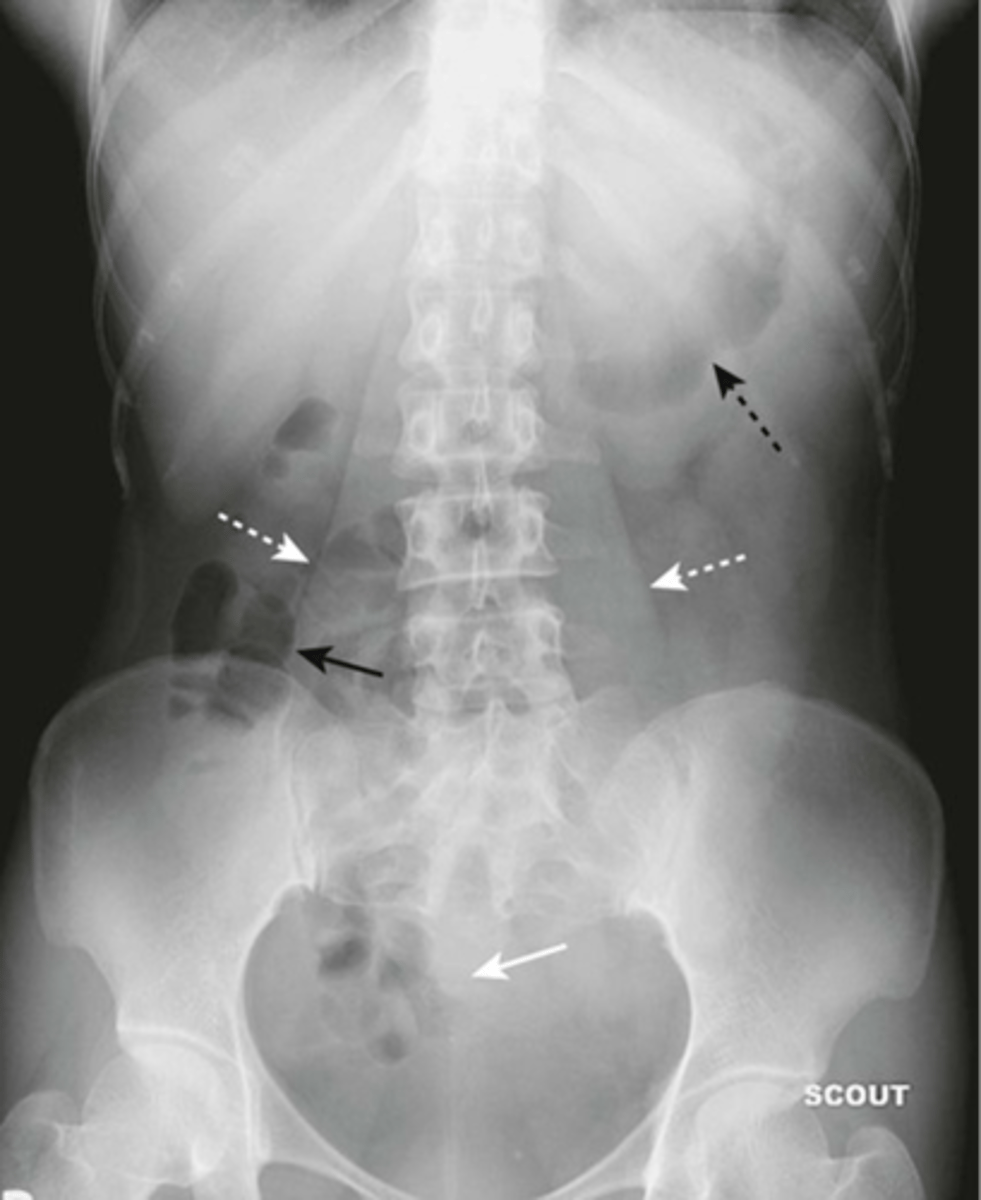

Abnormal organs on AXR

Hepatomegaly

Hepatomegaly (pic 2)